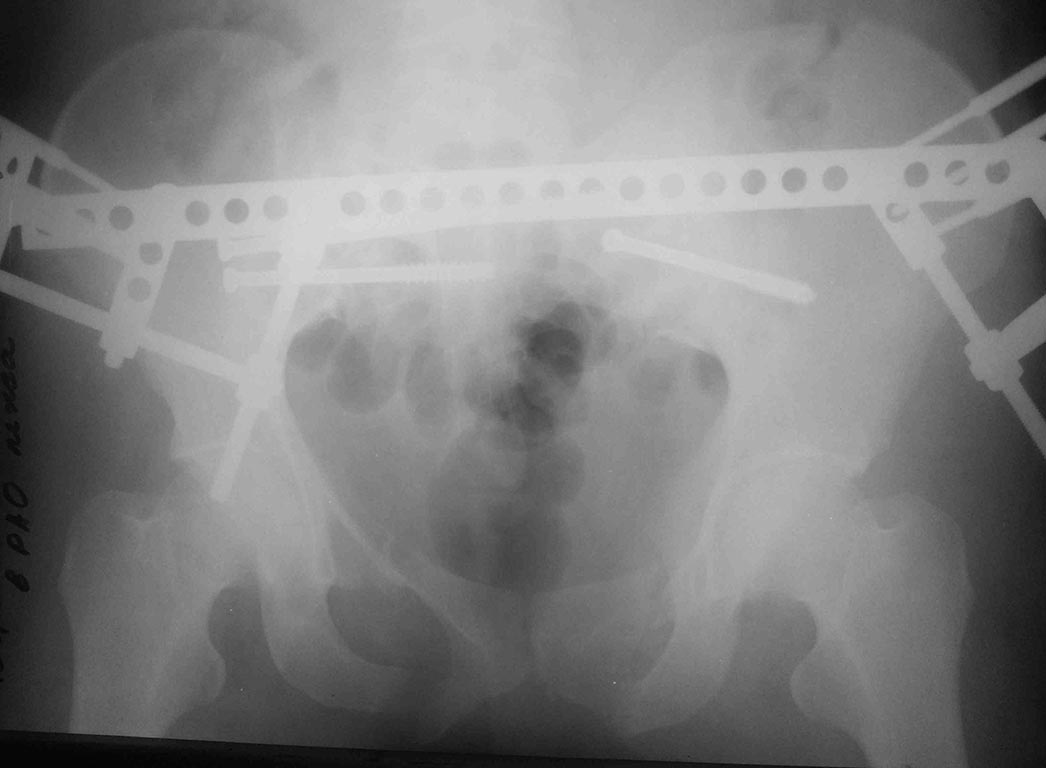

[Ortho] тяжелый таз 2

Уже обсуждалось http://weborto.net/forum/1384696698/

ближайший результат, все сделали закрыто, постараюсь сделать полноценные

снммки - это палатником.